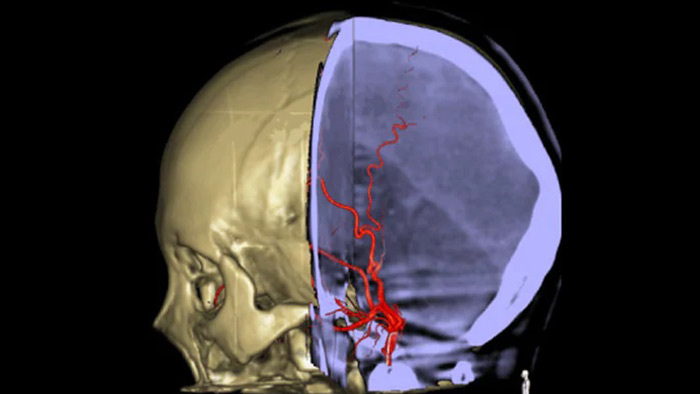

Анатомические ориентиры поддерживают точную 3D-навигацию

Smart CT

Технология SmartCT Roadmap предоставляет данные изображений анатомических структур, обеспечивая точность навигации при проведении к тромбу проводника, катетера и специального устройства.